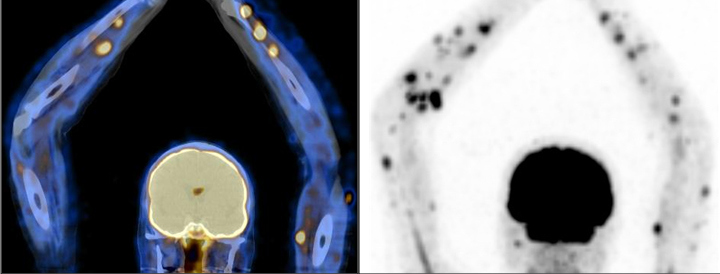

La grasa parda representa un hallazgo fisiológico que se observa con cierta frecuencia, distribuyéndose de forma relativamente simétrica y predominando en la región cervical, supraclavicular, dorsal y paravertebral (fig. 1).